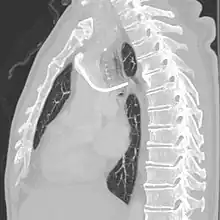

A port consists of a reservoir compartment (the portal) that has a silicone bubble for needle insertion (the septum), with an attached plastic tube (the catheter). The device is surgically inserted under the skin in the upper chest or in the arm and appears as a bump under the skin. It requires no special maintenance other than occasional flushing to keep clear. It is completely internal so swimming and bathing are not a problem. The catheter runs from the portal and is surgically inserted into a vein (usually the jugular vein or less optimally the subclavian vein). Ideally, the catheter terminates in the superior vena cava or the right atrium. This position allows infused agents to be spread throughout the body quickly and efficiently.

The port is then sutured on two sites to the underlying muscles. The tip of the catheter is checked for kinks and position using a fluoroscope. Besides that, aspiration of blood and contrast injection through the chemoport can also be used to confirm the position. The port is the closed in two layers (subcutaneous tissue is sutured first, followed by the skin). Sterile dressing is then placed on the port.[3] The optimum site to park the tip of the catheter is at the cavo-atrial junction or with margin of error of not more than 4 cm above the junction.[3]